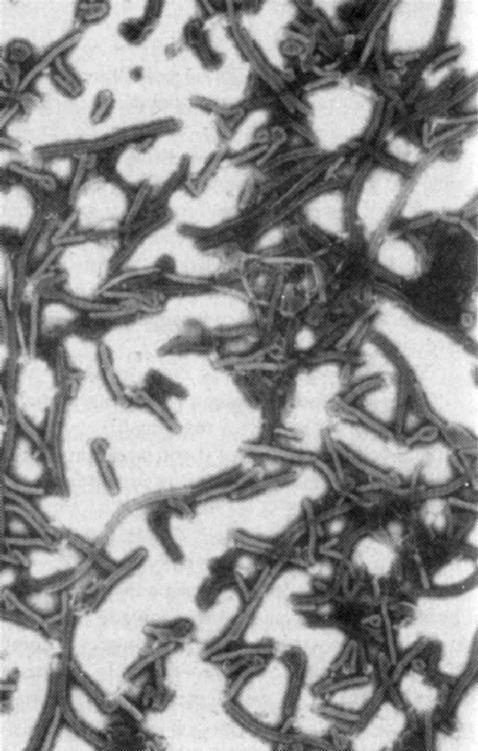

嗅闻过埃博拉病毒的彼得·耶林活了下来,他现在是研究所的首席科学家。他和汤姆·盖斯伯特遵循新病毒命名的传统,根据首次出现地点将其命名为雷斯顿毒株。他们在交谈时会随口称之为雷斯顿埃博拉。一天,耶林在他的办公室向我展示了某种埃博拉病毒的照片。病毒很像煮得尚有嚼头的意大利面条。“你看这个鬼东西。看这个长条混蛋,”耶林用手指勾出一个圈,“这是雷斯顿——天,险些又说成雷斯顿了——不,这是扎伊尔埃博拉病毒。问题在于,凭外表你很难分清这两个毒株。这就回到一个哲学问题上了:这两个毒株如此相似,为什么扎伊尔毒株对人类高度危险,而雷斯顿不危险呢?几乎可以肯定雷斯顿埃博拉病毒能通过空气途径传播。感染病毒的黑泽尔顿员工,我非常确定他们是通过空气感染的。”

扎伊尔埃博拉病毒粒子,放大17000倍。请注意一些粒子顶端的圈环,也就是所谓“牧羊人的曲杖”或“有眼螺栓”,这是扎伊尔埃博拉病毒及其姐妹的典型形态。拍摄者:托马斯·W·盖斯伯特,USAMRIID。

雷斯顿埃博拉病毒粒子。“问题在于,凭外表你很难分清这两个毒株。”——彼得·耶林。拍摄者:托马斯·W·盖斯伯特,USAMRIID。